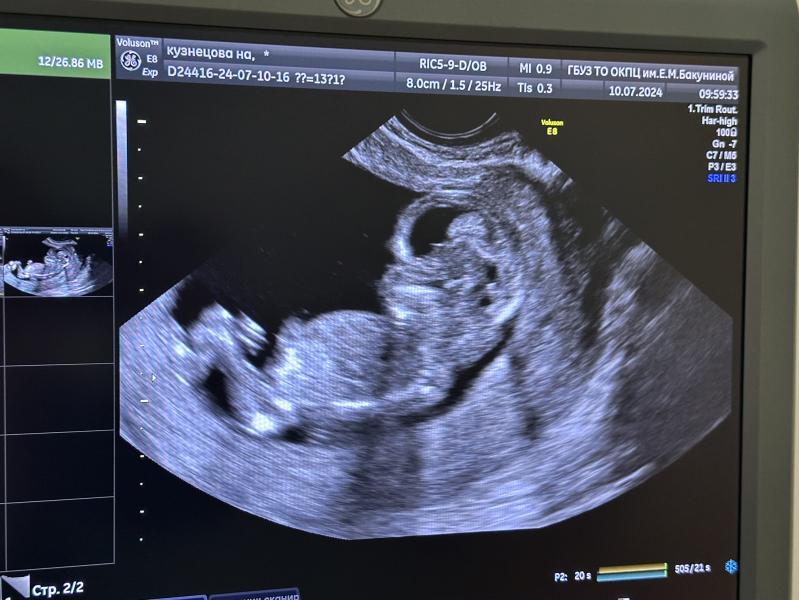

Первый скрининг: узи показало, что все хорошо, но кто там? Девочка или рано судить?

Первое узи, скрининг. Все хорошо, смотрю и думаю, вроде девочка? Или рано судить? Узист конечно не сказала , говорит рано

Не тот ракурс, чтобы пол можно было рассмотреть

К сожалению, фото не дали, на экране показали вот так и все🥲